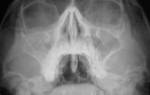

Врачи отмечают, что двустороннее воспаление гайморовых пазух, или синусит, может проявляться различными симптомами, такими как заложенность носа, головная боль, а также выделения из носа. Для диагностики заболевания важно учитывать не только клинические проявления, но и результаты рентгенографии или компьютерной томографии. Лечение синусита обычно включает назначение антибиотиков, если заболевание вызвано бактериальной инфекцией, а также противовоспалительных средств и деконгестантов для облегчения симптомов. В некоторых случаях может потребоваться промывание пазух или даже хирургическое вмешательство. Врачи подчеркивают важность своевременного обращения за медицинской помощью, так как запущенные формы заболевания могут привести к серьезным осложнениям. Профилактика, включая укрепление иммунной системы и своевременное лечение простудных заболеваний, также играет ключевую роль в предотвращении повторных эпизодов воспаления.